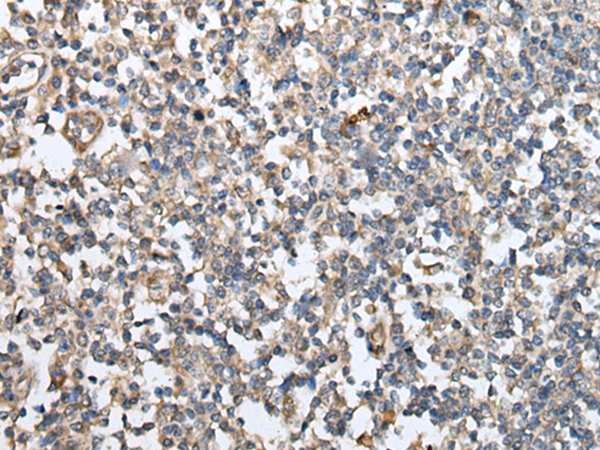

分类: 科研抗体货号: P05822别名: IFCR; MGA1; gp280应用: IHC反应种属: Human, Mouse